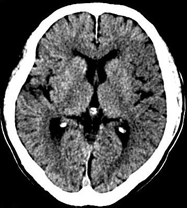

目前臨床對于16層CT的認可主要集中在三維成像領域上的突破.在16層CT的產品平臺上,常規(guī)掃描就能實現(xiàn)滿足三維成像的要求,因此16層也被稱為三維CT,三維成像給臨床診斷帶來了更精確更豐富的診斷信息,我們以臨床為例:

如上圖所示,相鄰的三張軸位圖像未見明顯異常,根據(jù)傳統(tǒng)軸位圖像很難得到準確的臨床診斷。

同一病人利用容積數(shù)據(jù)進行三維處理后,高品質MPR和三維圖像上則清晰顯示了縱向排列的腹腔干與腸系膜上動脈相鄰近,血管發(fā)生變 異,近端血管閉塞,為臨床提供了精確的診斷信息。

從上面的例子可以看到,能否為臨床提供高品質的三維影像成為了16層CT的核心價值,而東芝新一代的 全景三維16層CT擁有最為  先進的3項核心技術,在16層核心價值上的表現(xiàn)自然值得期待。